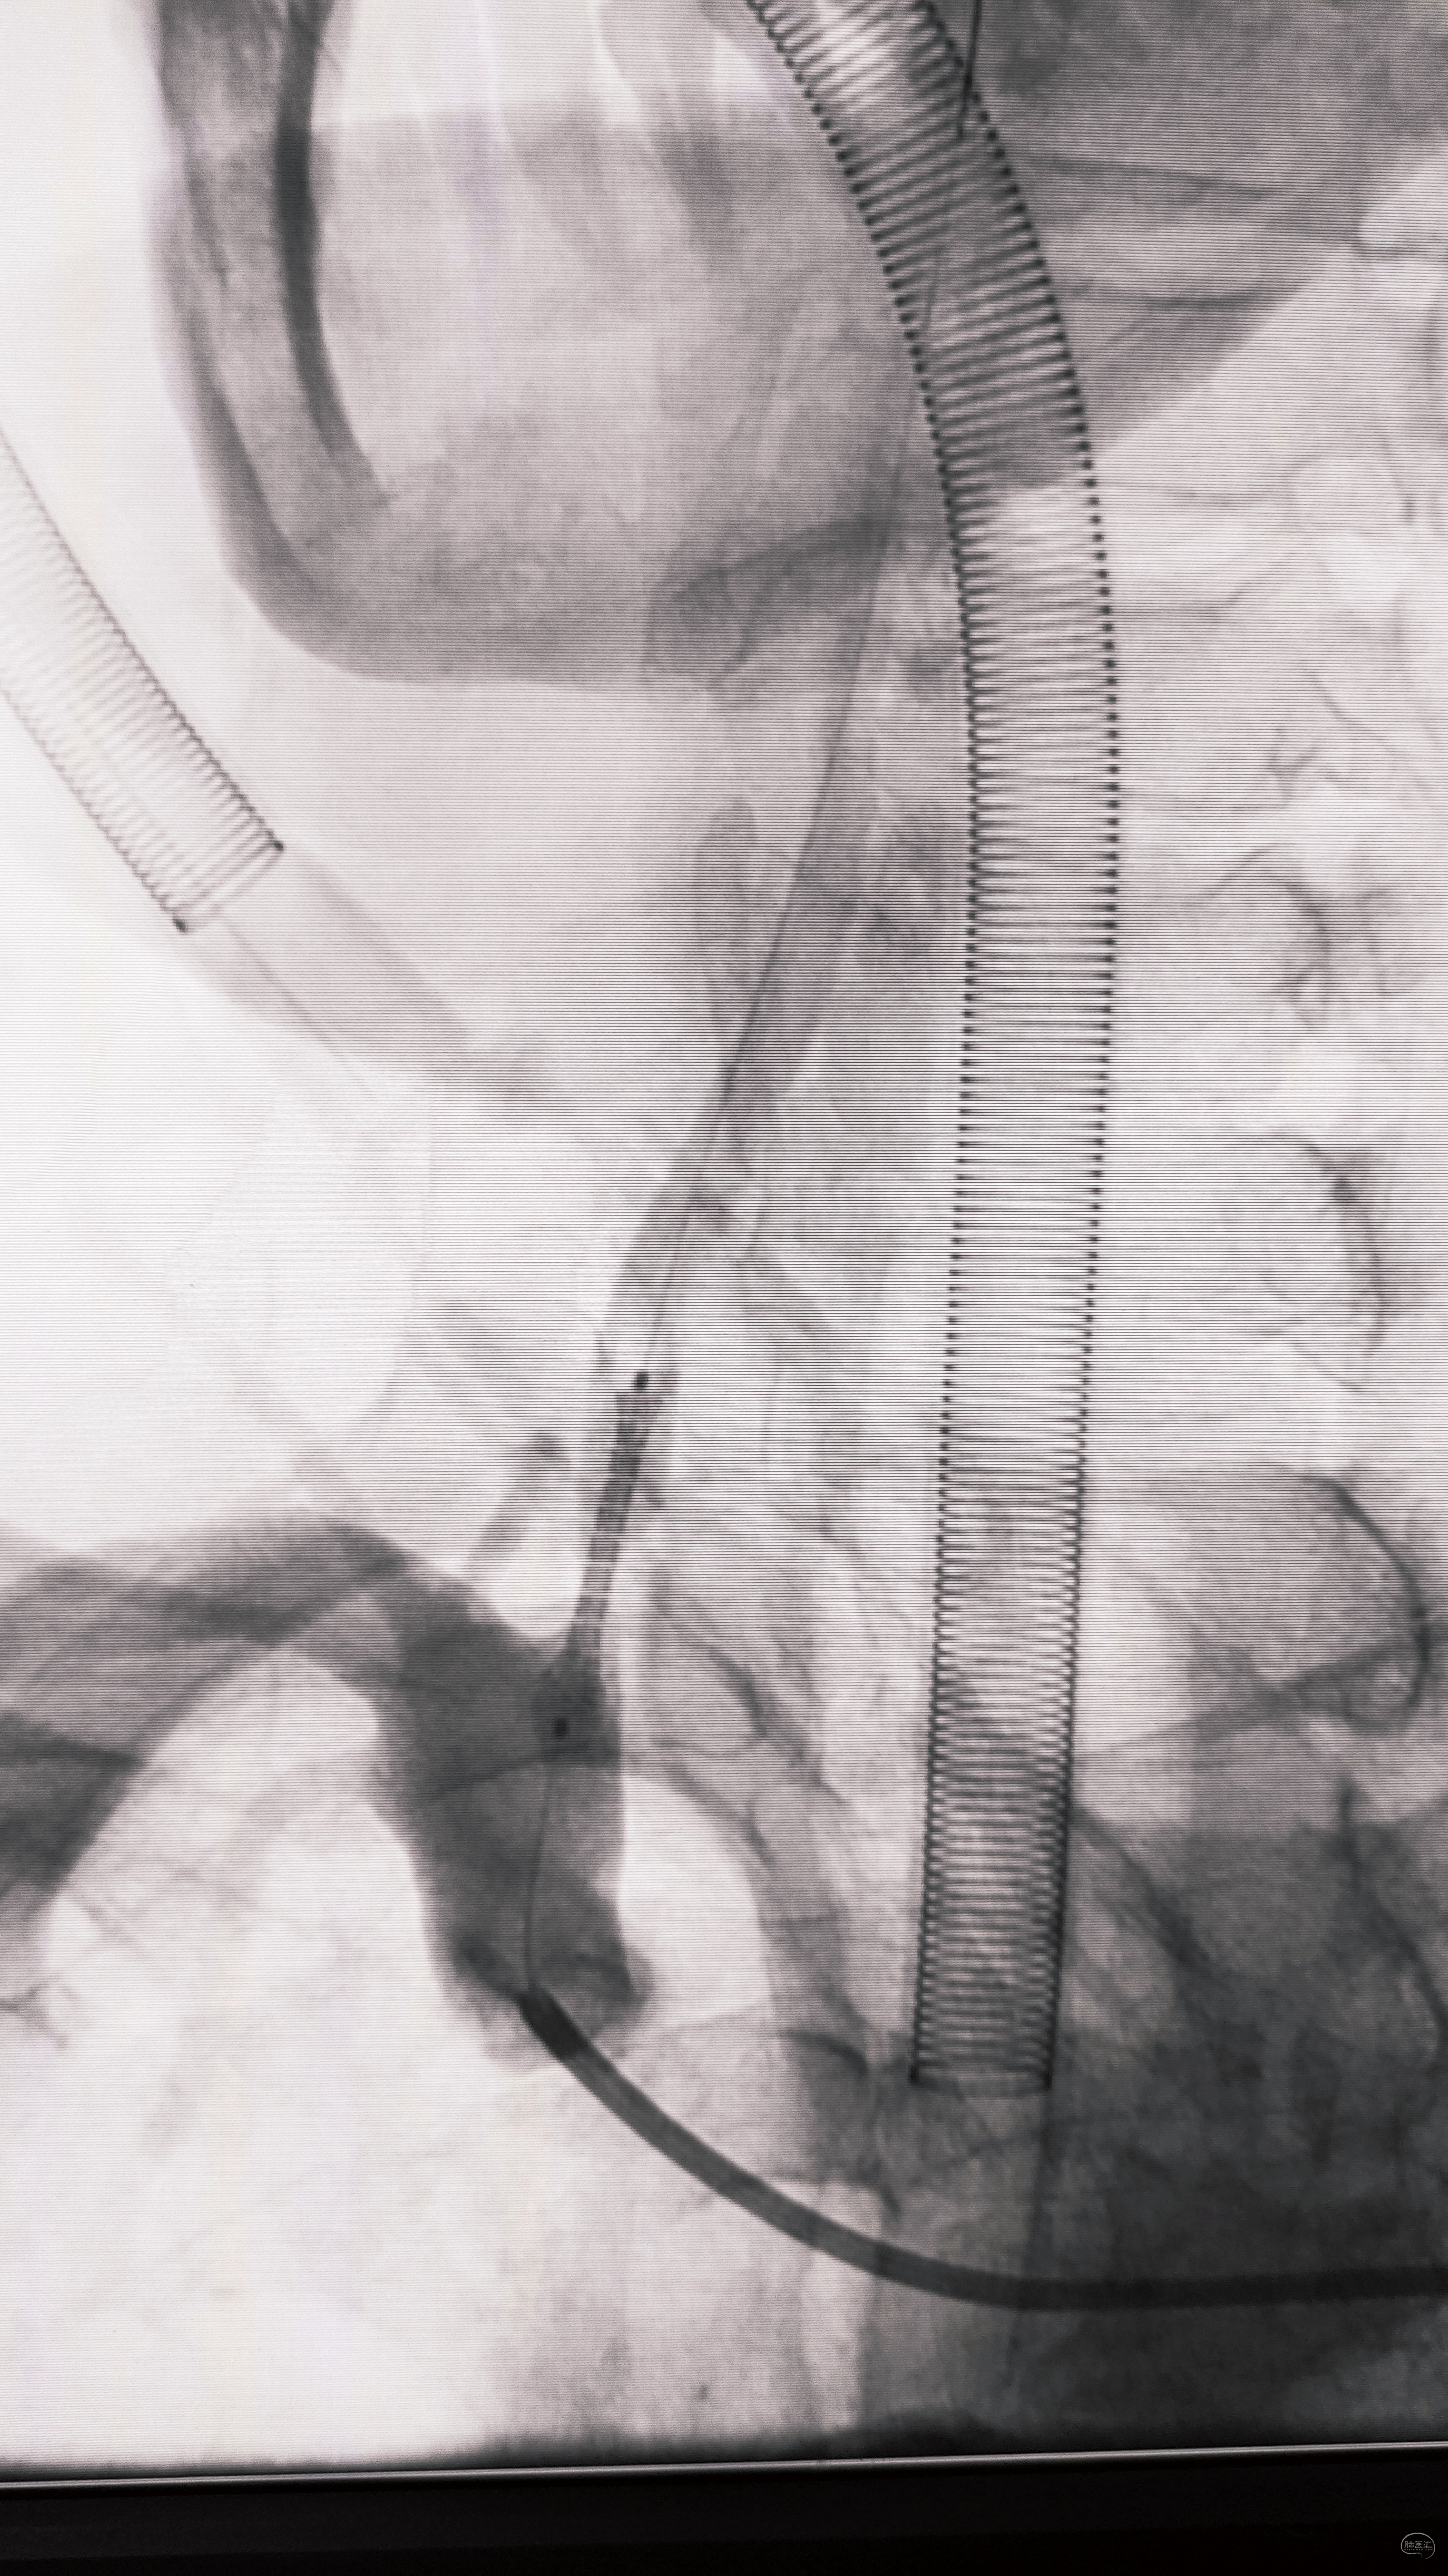

艰苦卓绝的吃线过程,此处心中浮现出一万个草泥马,最终,多角度+超选造影,验证真腔

小球囊+大球囊,梯度预扩

一切看似理想,一切看似简单,诡异的事情还是发生了,8F导引导管死活无法进入左侧锁骨下动脉,各种方法尝试个遍:泥鳅走远,单弯挂口,Sim挂口,屡战屡败(水平退步明显,不应该啊,夹层?),因为怕折腾,因为想安全,怕进假腔,弄出夹层。索性换一个思路:空中接力,构建桡-股动脉大环线

自下向上走不通,那就从上边来

经左侧桡动脉6F导引导管,出加长泥鳅,一路向下,逼近右侧股动脉鞘

以为很难,其实不然,泥鳅头段顺利进入股动脉鞘内,但是问题来了,因为是动脉鞘,有活瓣封口,泥鳅无法逆向穿过动脉鞘入口,何解?

那就利用换鞘技术,桡动脉侧持续给泥鳅张力并顶住(助手),缓慢回撤股动脉鞘至体外(主刀),看到泥鳅后抓紧,后拽;长度足够后,带套管重新置入8F股动脉鞘,完成桡-股动脉大环线建立。

泥鳅两段露头,8F导引导管沿泥鳅攀爬,一把干到左侧肱动脉为止

6F导引导管造影确认支架置入部位